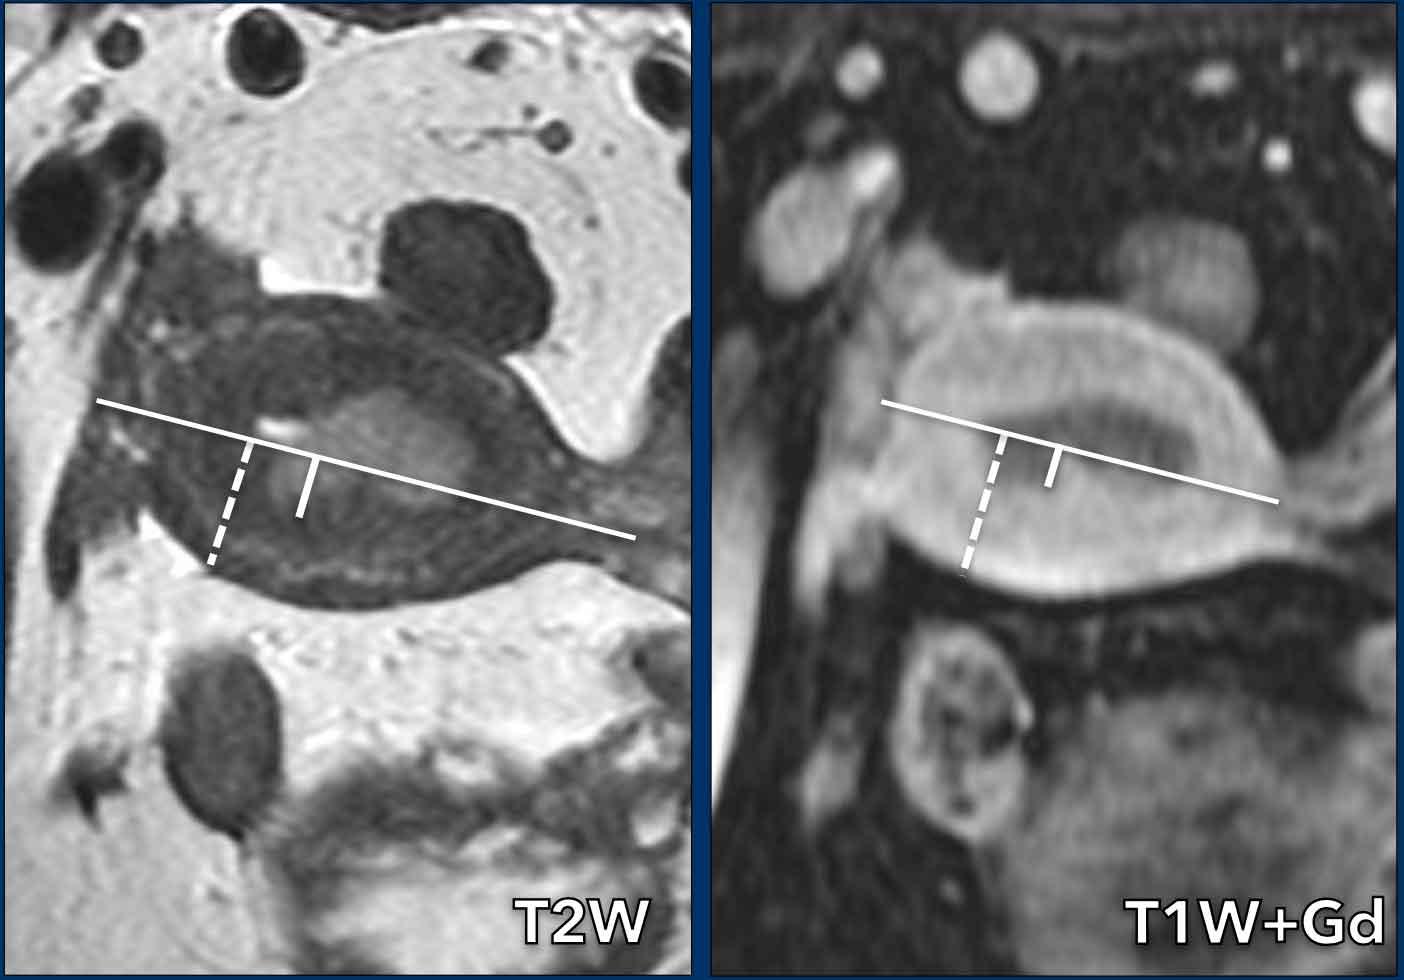

Đo độ sâu xâm lấn cơ tử cung thường được thực hiện kết hợp trên mặt phẳng đứng dọc (sagittal) và mặt phẳng ngang vuông góc (axial).

Quy trình gồm 3 bước (hình):

- Vẽ một đường thẳng song song với mặt trong cơ tử cung

- Đo mức độ xâm lấn tối đa của khối u vào cơ tử cung

- Xác định toàn bộ chiều dày cơ tử cung (đường nét đứt)

Tỷ lệ giữa bước 2 và bước 3 biểu thị phần trăm xâm lấn cơ tử cung.

Độ sâu xâm lấn < 50% toàn bộ chiều dày cơ tử cung được coi là xâm lấn ‘nông’.

Độ sâu xâm lấn > 50% được coi là xâm lấn sâu, liên quan đến nguy cơ cao hơn về xâm lấn khoang mạch bạch huyết, từ đó liên quan đến độ mô học cao hơn, nguy cơ di căn hạch và nguy cơ tái phát khối u tăng cao.

Lưu ý rằng theo phân loại FIGO mới, điều quan trọng là phải ghi rõ sự hiện diện hay vắng mặt của bất kỳ mức độ xâm lấn cơ tử cung nào, dù là nông hay sâu.

Việc không có xâm lấn cơ tử cung đặc biệt có ý nghĩa trong việc lựa chọn bệnh nhân đủ điều kiện điều trị bảo tồn khả năng sinh sản (xem phần bảo tồn khả năng sinh sản bên dưới).

Hình ảnh

Xâm lấn cơ tử cung được biểu hiện bằng sự gián đoạn tín hiệu giảm bình thường của vùng chuyển tiếp trên chuỗi xung T2W và sự gián đoạn ngấm thuốc của ranh giới nội mạc-cơ tử cung trên hình ảnh sau tiêm thuốc tương phản từ, trong đó ung thư nội mạc tử cung biểu hiện giảm tín hiệu so với cơ tử cung ngấm thuốc.

Cơ tử cung có toàn bộ chiều dày 21 mm, nhưng mức độ xâm lấn vào cơ tử cung chỉ là 6 mm (6/21=28%, cho thấy xâm lấn < 50%).